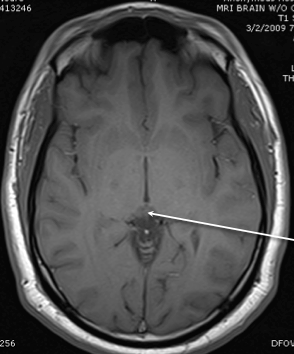

pineal body

lateral horn

inferior ventircle

thalamus